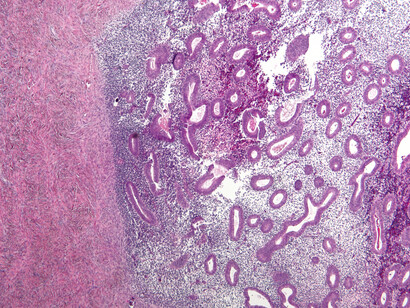

Endometriosis

Si al bajar el período te duele tanto que tienes que parar tu vida unos días cada mes, algo no va bien. ¿A ver si te sientes identificada? Tienes un malestar intenso con dolores punzantes en el abdomen, espalda baja y pelvis, y síntomas como la fatiga, problemas intestinales y cambios en los patrones de menstruación. ¿Sí? Pues eres candidata a sufrir endometriosis.

Es una enfermedad que padecen entre un diez y un quince por ciento de las mujeres. Como ves, es más habitual de lo que parece y le puede pasar a cualquiera de nosotras.

Se produce cuando el revestimiento del útero (el endometrio) es muy rebelde y decide crecer en lugares donde no debería, como en los ovarios, las trompas de Falopio e incluso en otros órganos. Al llegar la regla, estos tejidos "rebeldes" también sangran y causan dolor, inflamación y, en algunos casos, la formación de tejido cicatricial (llamado tejido fibroso o adherencias).